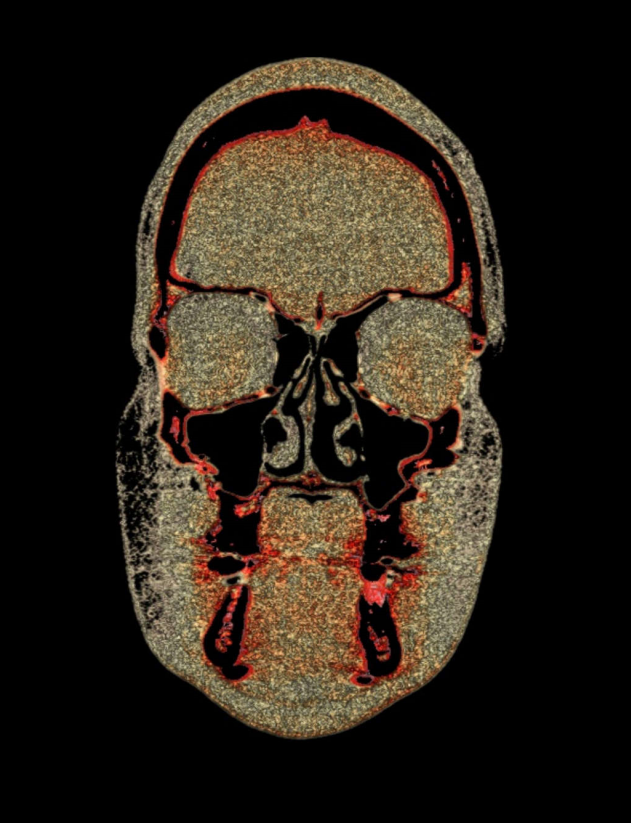

TC de face (do Hióide à Glabela), reconstrução 3D do tecido ósseo, radiografia panorâmica, telerradiografia lateral com traçado, cortes transversais e axial de maxila e mandíbula e arquivo DICOM- entregue em pasta de Pvc.

TC de face (do Hióide à Glabela), reconstrução 3D do tecido ósseo, radiografia panorâmica, telerradiografia lateral e frontal com traçado, cortes transversais e axial de maxila/mandíbula e arquivo DICOM – entregue em pasta de Pvc.

TC de face (do Hióide à Glabela), reconstruções 3D do tecido mole/ósseo/vias aéreas, radiografia panorâmica, telerradiografia lateral e frontal com traçado, cortes transversais e axial de maxila/mandíbula, ATM e arquivo DICOM – entregue em pasta e caixa de Pvc.